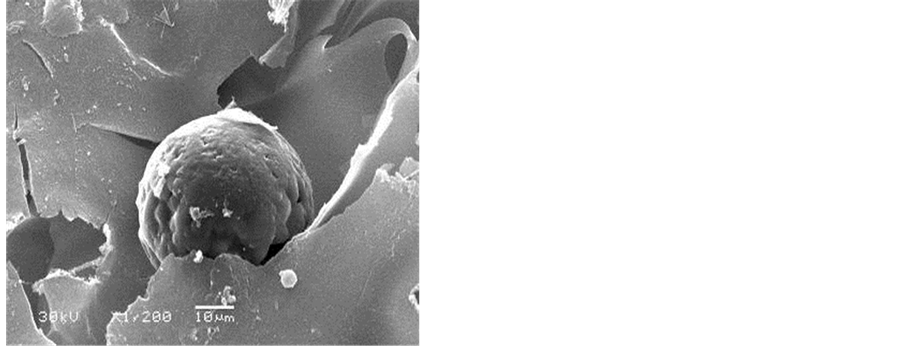

4.1. SEM Observation of the Silk Fibroin Scaffold before and after Adipogenic Induction

The silk fibroin scaffold possesses a natural porus 3D spatial structure, the aperture is uniform in the internal scaffold, and interconnected each other, the aperture is 50 - 60 μm, the porosity is up to 90% (Figure 1). After adipogenic induction culture for 2 weeks, the hUCMSCs differentiated into rounded adipocytes and a lot of extracellular matrix secreted.

Figure 1. Silk fibroin scaffold under SEM, before and after coculture with hUCMSCs. (a) Silk fibroin scaffold (SEM, ×200); (b) Cell-scaffold complex, 2 weeks after adipogenic induction (SEM, ×900).

4.3. The Result of Coculture of hUCMSCs with Silk Fibroin Scaffold

The hUCMSCs showed rounded adipogenic cells under SEM, after adipogenic culture in silk fibroin scaffold in insulin-IRES-EGFP gene transfection group (A) and EGFP gene transfection (group B), secreting a lot of extracellular matrix and covering the scaffold material completely (Figure 3) under the fluorescent inverted phase- contrast microscope. After Oil Red O staining, a lot of adipocytes appeared in silk fibroin scaffold, round adipose droplets showed intracellularly, the size of the adipocytes was not homogenous; the density of adipocytes in group A are much more higher than that in group B, be equal to the (1.6 ± 0.2) times of group B (Figure 4, Figure 5). The difference of the cell density between the two groups was significant (P = 0.007, P < 0.01).

Scaffold is the key factor in the construction of tissue engineering tissues. In this study, we chosed silk fibroin as the scaffold, it possesses a good property of mechanic and biocombatibility, biodegradation, rich source and very cheap. Hofmann’s experiment revealed that silk fibroin could not only combine with MSCs in vitro, but also adhere to the preadipocytes and maintain the shape of preadipocytes [26] . On the immunogenicity, Wang [27] reported that during the whole implantation period, all the scaffold showed a good compatibility, the reaction between the animal and the grafts was minimal. Our previous study revealed that an aperture of 50μm of the silk fibroin was of choice in the construction of tissue engineering adipose [28] . Under SEM, the silk fibroin scaffold possesses natural porous 3D spatial structure, the aperture is uniform in the internal scaffold, interconnecting with each other, an aperture of 50 - 60 μm, a porosity of 90%, hUCMSCs adhered to the scaffold tightly, grew well, and secreted extracellular matrix. The result of the experiment showed that the scaffold was good for the cell growth. The activity of hUCMSCs in silk fibroin sccaffold after gene transfection by MTT test showed that the difference of the absorbance in cell group and in cell scaffold group, was not significant (P = 0.066, P > 0.05). These results revealed that the silk fibroin scaffold was not toxic to the growth and proliferation of hUCMSCs after gene transfection.